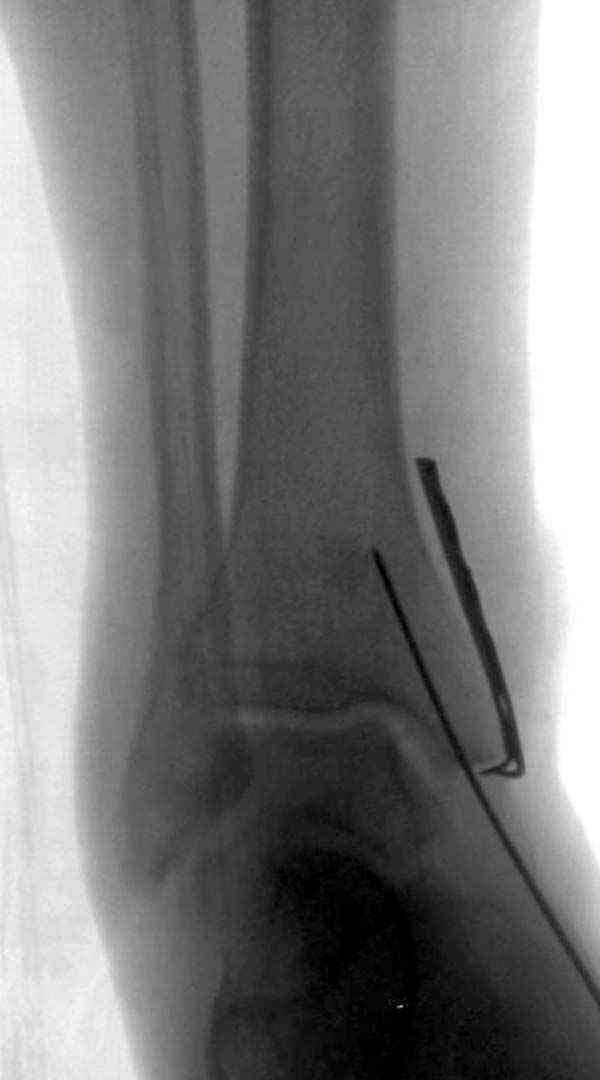

Случай прошлого года:пациентка-молодая ,крупная женщина ,30лет.Травма в начале апреля 2009г-пронационный перелом лодыжек с подвывихом стопы.Ко мне обратилась через 35 дней,прооперирована 22.05.2009г.Внутренняя лодыжка фиксирована по Веберу,наружная реконструктивной пластиной с наложением болта-стяжки.Иммобилизация "сапожок" в течении месяца,затем пригипсовано "стремя".Гипс снят 10.07.2009г

Достаточно быстрое восстановление функции.В октябре 2009г-почувствовала боль,в области рубца над гайкой открылся свищ.На Р-граммах-консолидация переломов и смещение гайки по стяжке.10.11.2009г-конструкции удалены,санация,заживление ран.В настоящее время пациентку ничего не беспокоит.На операции-раскручивание гайки-болталась на конце стяжки.Вопросы:какой механизм раскручивания и что я неправильно сделал?Свои версии:1)в области синдесмоза успела образоваться рубцовая ткань,которая при движении в суставе"пружинила",поскольку голеностопный сустав является спиральным, то и биомеханика подобна кривошипному механизму.2)Реконструктивная пластина не "реконструировалась" по форме лодыжки.Наложил,как есть.То есть подпружинивала сама пластина.Ну,это мои догадки.Что нужно,чтобы избегать впредь таких,пусть и не "страшных"осложнений:Рассверливать через лодыжку область синдесмоза?Ставить шайбу-гровер?Тщательно моделировать пластину?Прилагаю сравнительные снимки-сразу после операции и перед удалением конструкции.

Визуально никаких вопросов по репозиции не было.Да и на основании чего сомнения,что наружная лодыжка не полностью репонирована или прорезалась проволка ???Я не вижу...Снимок после репозиции справа.

Раз ,есть желание посмотреть другую проекцию выкладываю-ну лучшего качества нет...